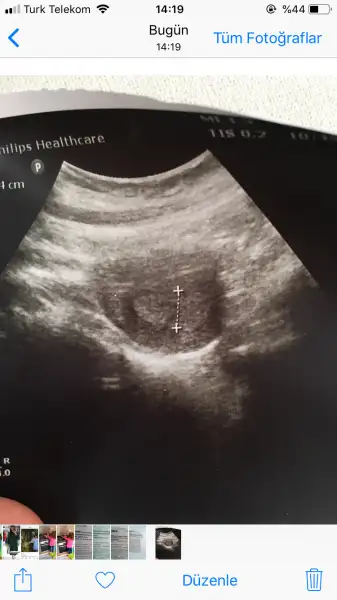

5+5im canım sata göre. Bak buda ultrason fotom doktor kese yok ama oluşmaya çalışıyor gibi Rahim kalınlaşmış demişti